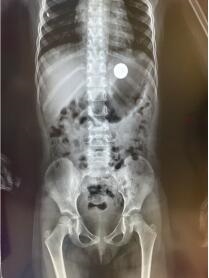

“梁主任,有一个4岁的小女孩误吞了1枚硬币,x光片显示有一个圆形不透光异物在胃内,你看能不能用消化内镜给小朋友取出来?”近日,已下班回家的三六三医院消化内科主任梁红亮博士突然接到了电话。“好的,我马上就到”。放下手机,梁红亮便拿起外套,戴上口罩向着三六三医院的方向飞驰而去。

“在胃底,和食物混在一起了”李杭娟护士的话语打破了此时的沉寂。只见一枚硬币“躺”在胃底,清晰可见,“快,异物网篮”。梁红亮和李杭娟默契的配合,把异物网篮插入,在胃内张开,慢慢的伸到硬币旁准备将其套进网篮中。一次、两次均未成功,第三次,试着调整角度,慢慢将硬币全部放进了异物网篮的中间,屏住呼气,再次慢慢拉紧收回,硬币便服服帖帖的被异物网篮套牢。梁主任用最轻的力气,缓缓地抽出胃镜,通过第一个、第二个、第三个生理狭窄,小心翼翼地抽出胃镜,将取出的硬币放在纱布上,大家一直紧绷着的心才放了下来。